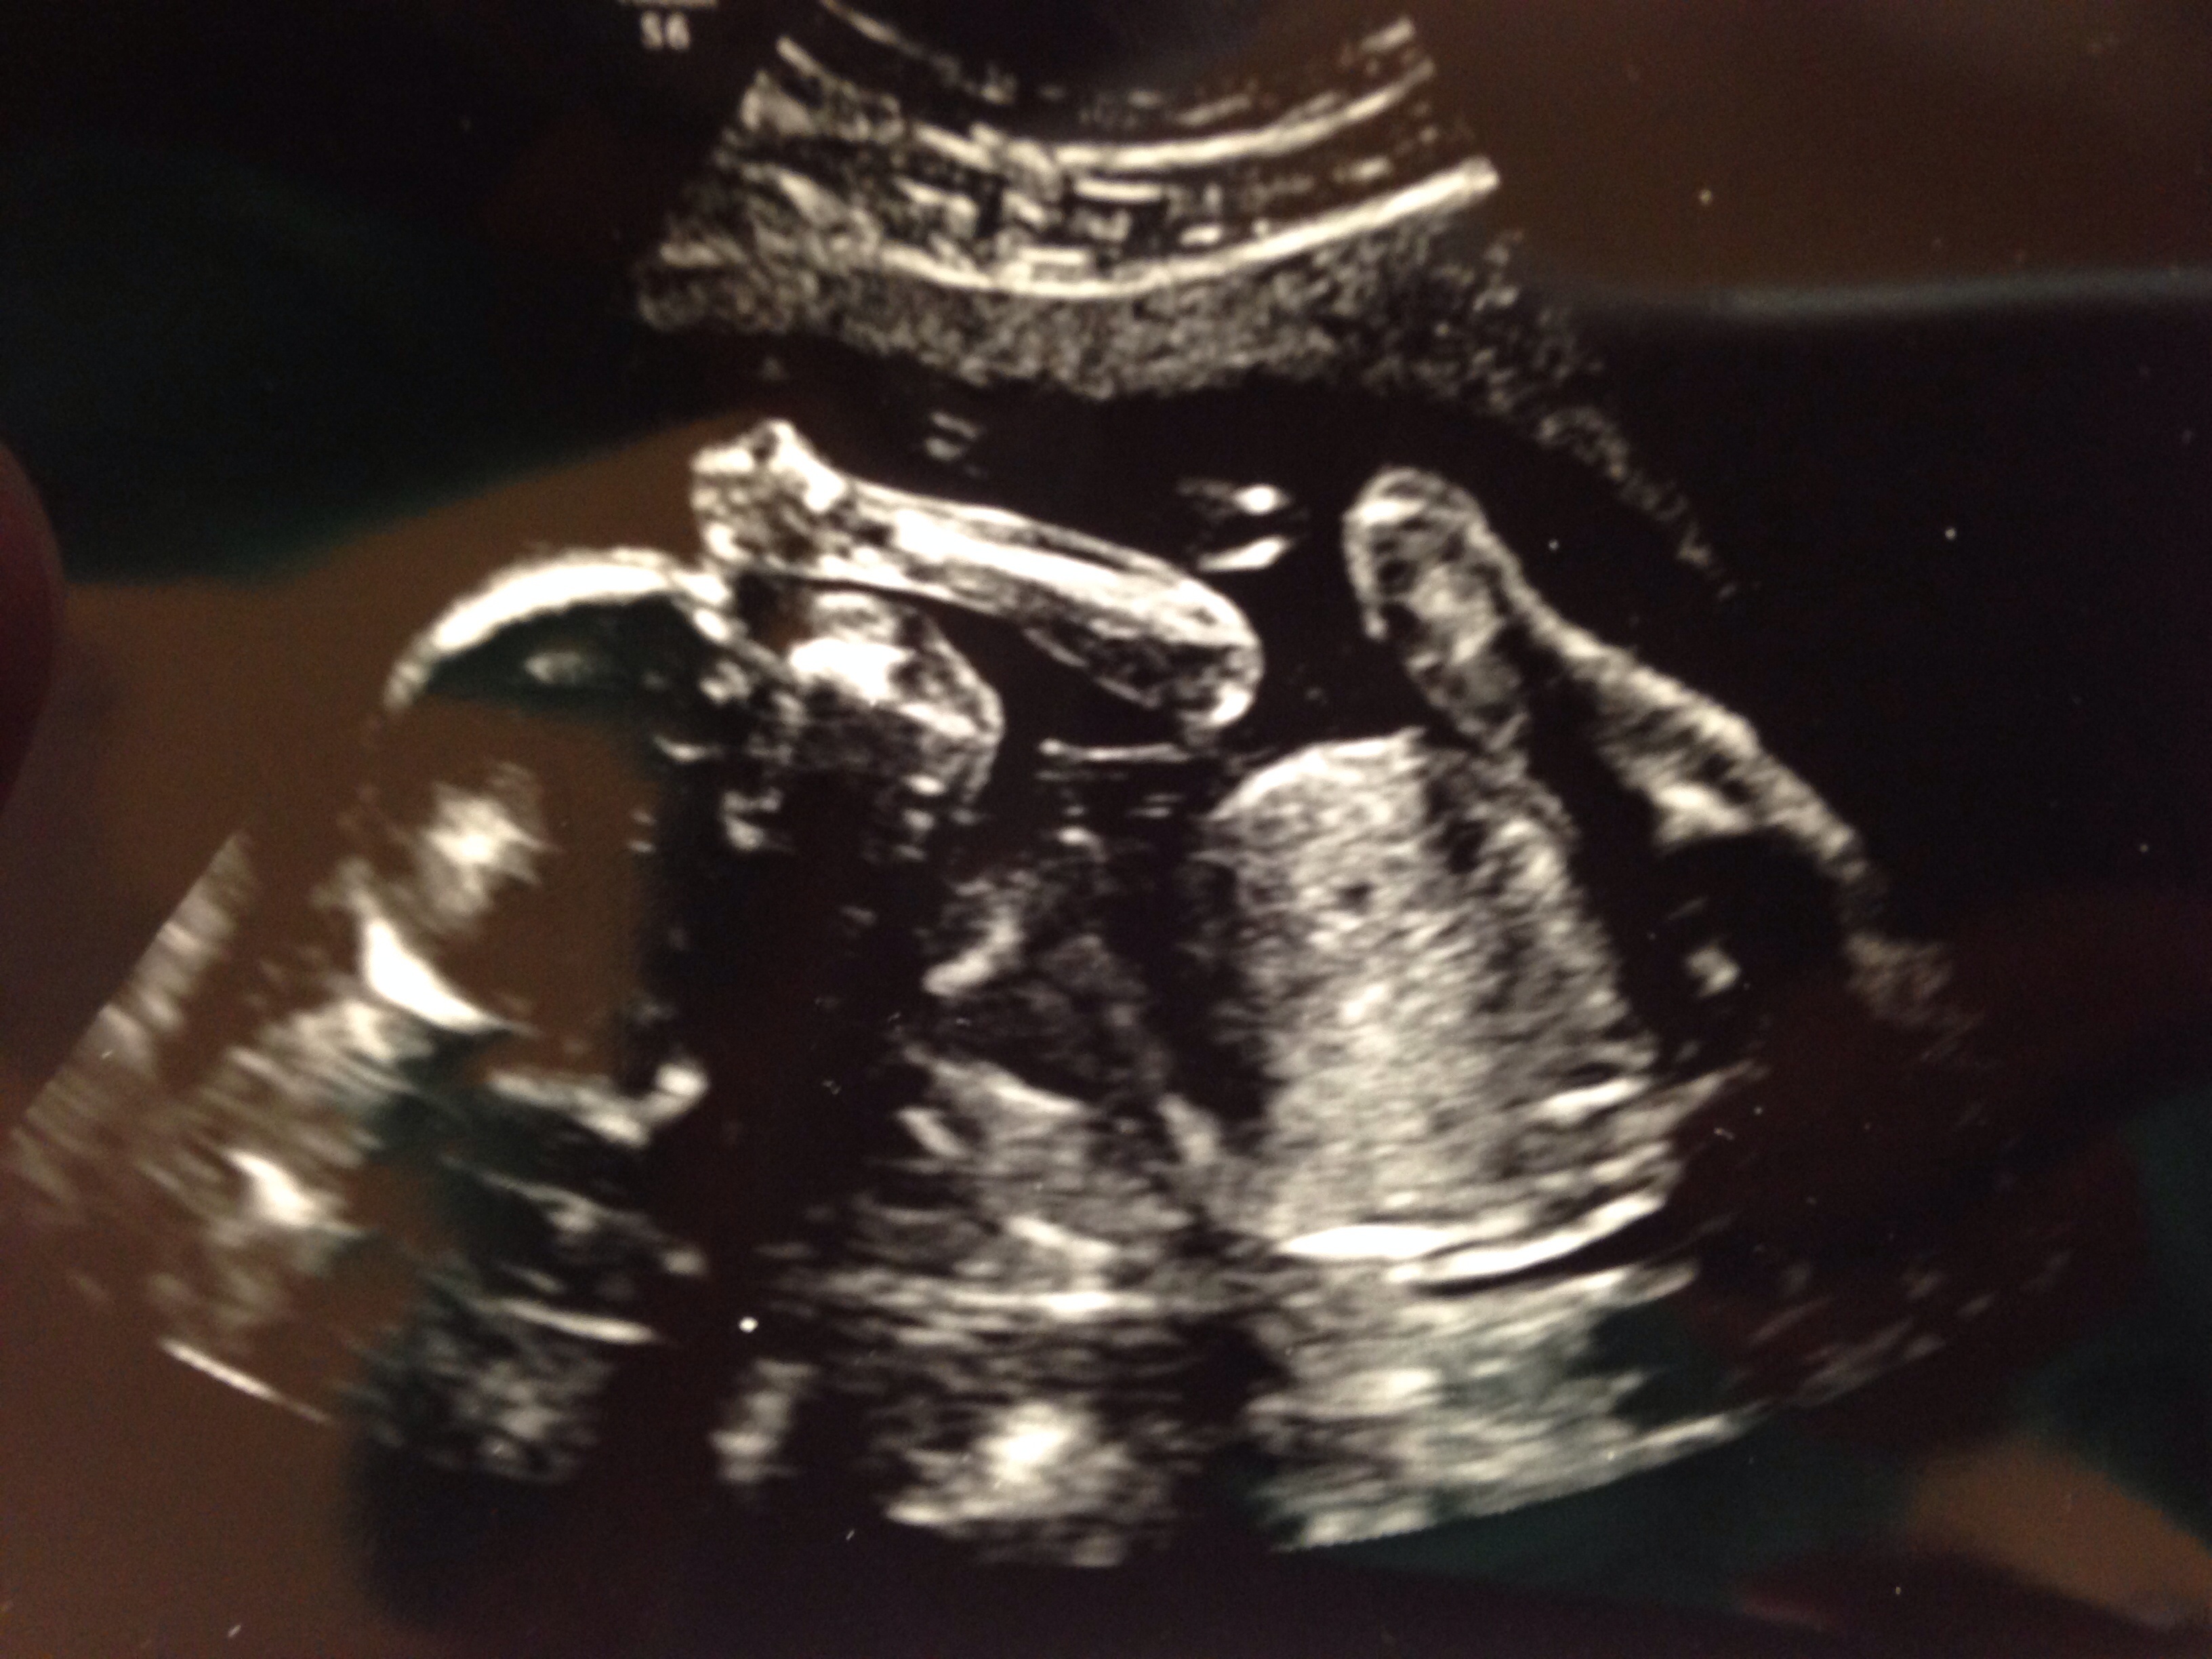

Also, from our u/s 3 weeks ago. Love the little foot that has been kicking me a lot more now!

I love the u/s of him crossing his feet!